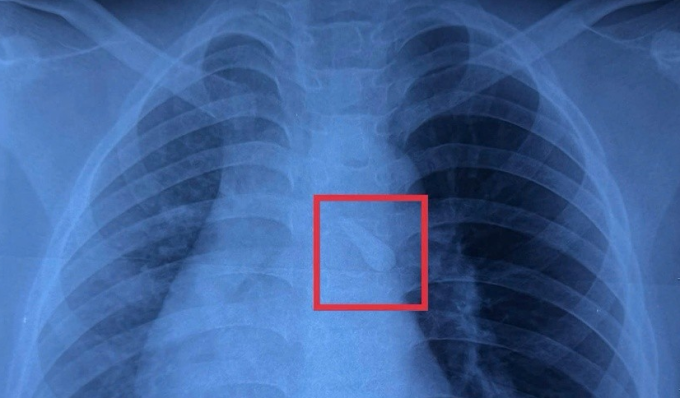

Ngày 29/12, BS.CK1 Lý Phạm Hoàng Vinh, Khoa Tai Mũi Họng, Bệnh viện Nhi đồng 1, cho biết kết quả X-quang ghi nhận một dị vật cản quang trong khí quản của bé. Khám hàm mặt cho thấy mất răng số 21, từ đó các bác sĩ nghi ngờ chiếc răng gãy đã bị bé hít sặc vào đường thở sau chấn thương.